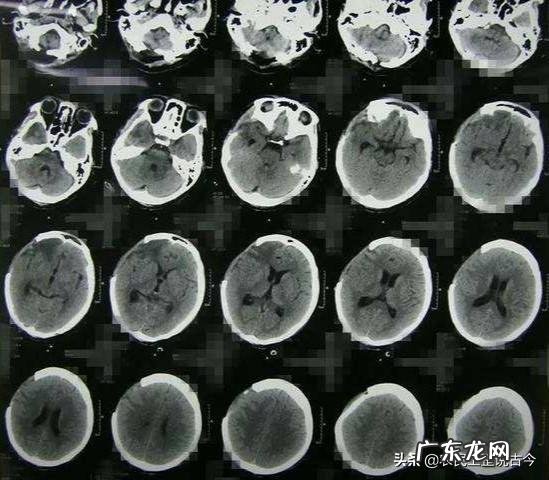

为了搞清楚这个问题,韩康信教授找到了山东大学齐鲁医院神经外科的鲍修风教授 。鲍修风教授是神经外科的全国顶尖专家,主任医师、教授、博士生导师 。他看到这些颅骨之后也颇为诧异,孔洞边缘光滑、看着似乎并不像是死后所打 。但是,一切必须用事实说话,鲍修风教授查阅了历年来许多例开颅手术患者定期复查的CT影像资料 。最后得出结论:这些史前人类颅骨上的孔洞是生前所打,部分颅骨的主人在开颅之后起码生存了数月以上、甚至更久 。

鲍修风教授的依据是什么呢?颅骨切口愈合与软组织不同,它是由颅骨内板、外板围绕中间的板障生长,等内板和外板生长连接到一起、包裹板障之后,切口便愈合不再生长,前后大约需要数月 。故而,开颅手术切口在彻底愈合之后比刚刚开颅之时或死后开颅者要光滑、圆润 。如果那些史前人类头骨上的孔洞是死后所打,不可能出现内板、外板围绕板障生长愈合的表现 。鲍修风教授因此得出结论,被开颅的史前人类,在开颅之后起码存活了数月、甚至更久的时间 。这一结论对于传统中医外科能够开展开颅手术的问题,几乎是颠覆性的!史前人类都可以开颅并使被开颅者存活数月以上,华佗为何不能呢?